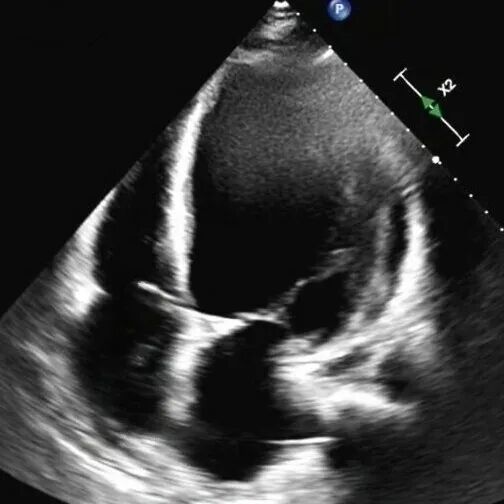

术前心脏超声

61岁的李先生(化名)三年前就偶尔出现胸闷乏力,一个月前,他因夜间无法平卧、呼吸极度困难,被紧急送往beat365中文在线官网第一附属医院(第一临床医学院)心脏重症监护室。通过系统检查,李先生左室舒张末期内径102mm(男性的正常值≤55mm),主动脉根部瘤样扩张63mm(正常≤35mm),左室射血分数仅21.83%(正常≥50%),心功能IV级(NYHA分级),主动脉瓣重度关闭不全,二尖瓣轻-中度关闭不全,最终确诊为终末期心衰,巨大心脏,主动脉根部瘤样扩张,随时发生主动脉夹层/主动脉破裂危及生命,此外主动脉瓣重度关闭不严,心功能极差,心脏随时可能“停摆”。